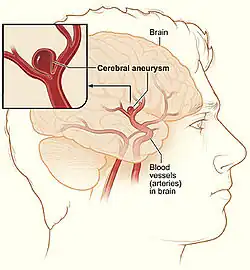

Aneurisma cerebral é a doença na qual um segmento de vaso sanguíneo, quase sempre de uma artéria do Polígono de Willis, encontra-se anormalmente dilatado no encéfalo. A dilatação é causada, em geral, por uma falha muscular da parede de uma artéria, ou muito mais raramente, de uma veia. O tamanho de um aneurisma cerebral é variável. Pode ser pequeno, de poucos milímetros até 1 cm, tamanho médio, até 2 cm e maiores (grandes ou gigantes), atingindo vários centímetros na sua maior extensão. Há diversos formatos, geralmente saculares, mas podem ser também irregulares ou fusiformes.

Localizações

A localização mais comum dos aneurismas cerebrais é nas artérias da base do cérebro, conhecidas como Polígono de Willis. Aproximadamente 85% dos aneurismas cerebrais se desenvolvem na porção anterior do círculo de Willis, envolvendo as artérias carótidas internas e seus ramos maiores que vascularizam as porções anterior e média do cérebro. Os locais mais comuns incluem a artéria comunicante anterior (30-35%, geralmente em homens; a bifurcação da carótida interna e artéria comunicante posterior (30-35%)geralmente em mulheres; a bifurcação da artéria cerebral média (20%), a bifurcação da artéria basilar e as outras artérias que fazem a circulação posterior (5%).